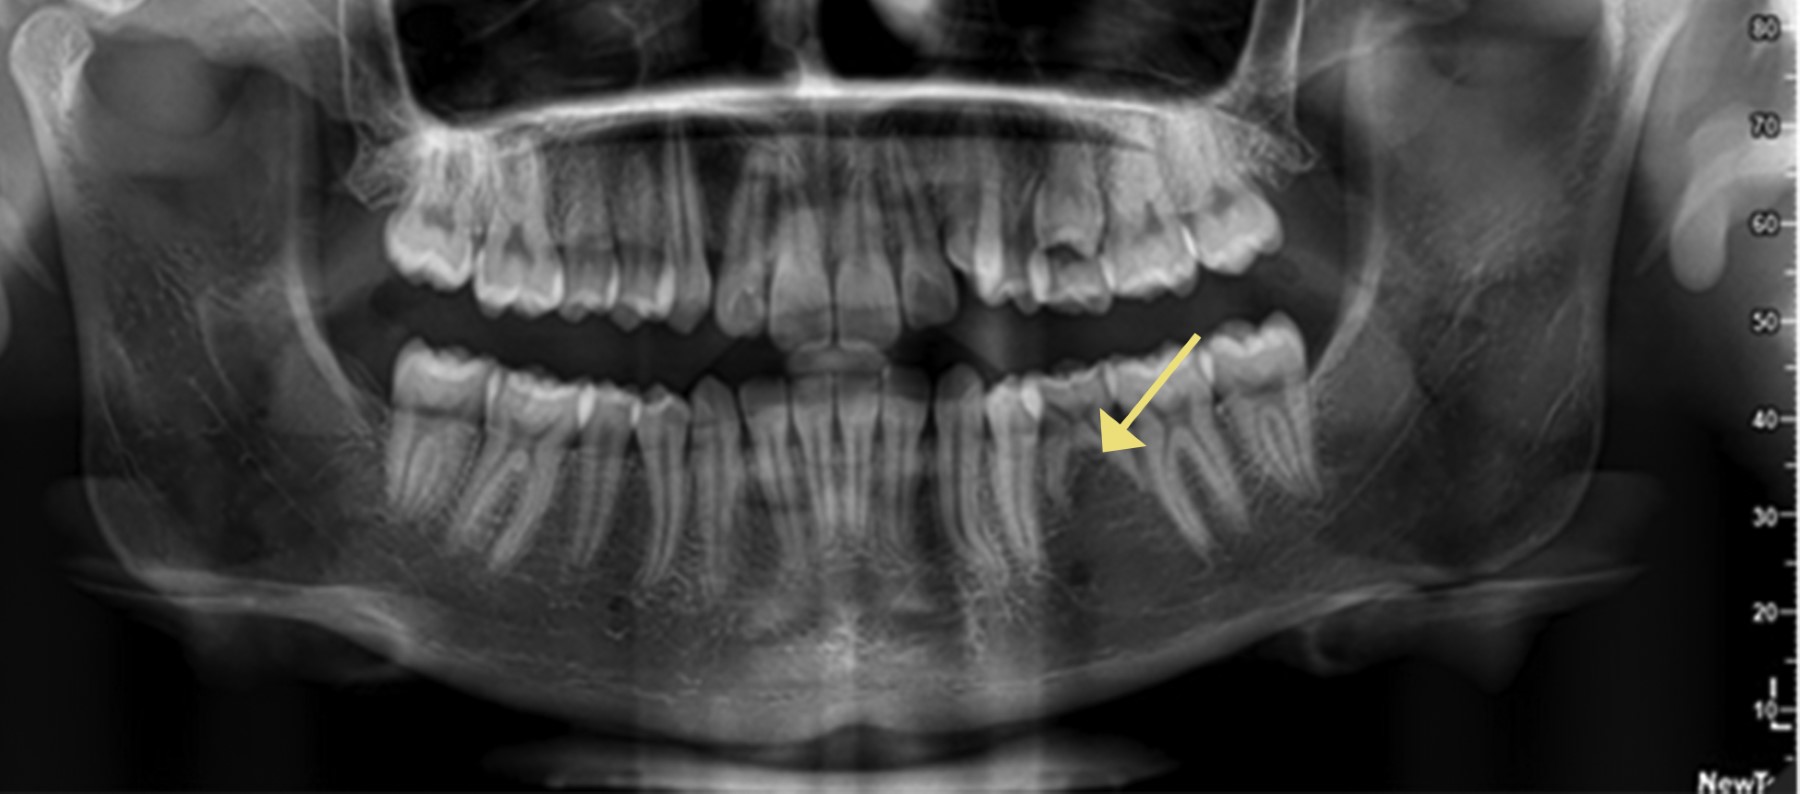

La historia clínica odontológica abarcó aspectos clínico patológicos, antecedentes heredofamiliares y preguntas relacionadas con su salud bucal, para el correcto llenado de ésta se realizó una inspección clínica extraoral, donde se puso atención a los tejidos de origen ectodérmico incluida la piel, cabello, uñas, glándulas sudoríparas y oídos para descartar un posible síndrome que el paciente pudiese desconocer. Para corroborar diagnósticos de ADNS se solicitó un examen radiográfico específicamente una ortopantomografía, esta imagen nos aportó información múltiple del estado general del paciente, la existencia de patología o la presencia o ausencia de órganos dentarios (Figura 1). Por último, se obtuvieron 10 µL de sangre capilar del dedo anular que se recolectó en tubos foliados que contenían 100 µL de NaOH (hidróxido de sodio) para someter la muestra a lisis alcalina para la genotipificación de los polimorfismos.

La frecuencia de hipodoncia fue de 12.9% del total de la población revisada, mientras que la ausencia de algún tercer molar se encontró en 25.9%. Cabe aclarar que hubo participantes que se colocaron en ambas categorías, ya que presentaban hipodoncia más la ausencia de algún tercer molar. La agenesia de terceros molares fue el rasgo que más se manifestó en la población, especialmente en las mujeres, mientras que la hipodoncia fue más frecuente en hombres (Tabla 4). El órgano dentario más afectado fue el 18, seguido del 28 y 48. Los menos frecuentes fueron el 25 y 45. No se observó ningún primer premolar superior e inferior que estuviese ausente (Figura 3).